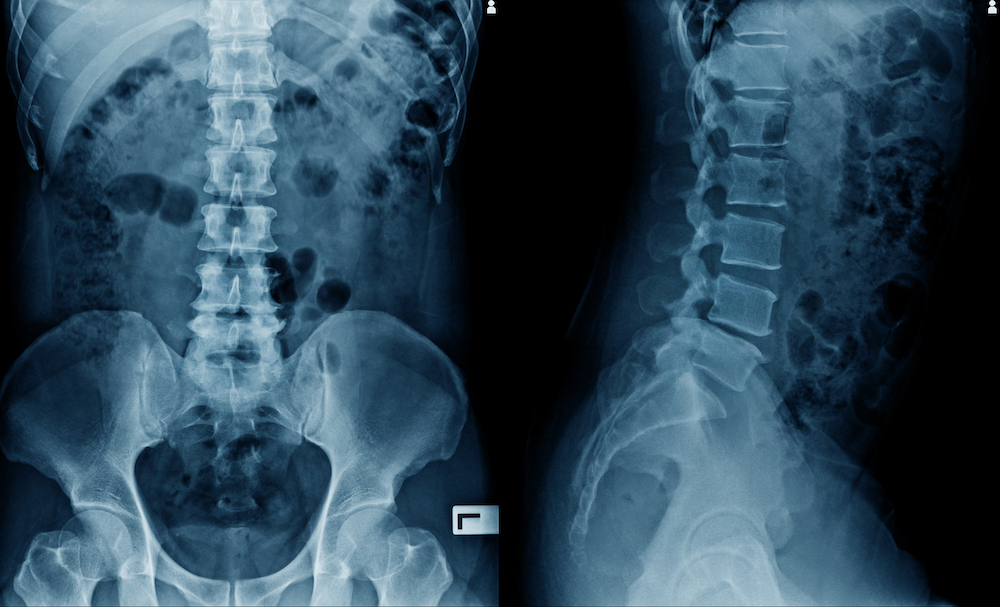

X-rays of your spine gives us an extremely detailed look at what’s going on with your spine. Not only does it show us the underlying condition, but also shows us the exact position of the bones along with any permanent tissue damage (arthritis). This helps Dr. Craig Schulman make a correct diagnosis along with creating an accurate, smart, care plan that is appropriate for your condition.

If you’ve been experiencing back pain, neck pain, headaches, or any other problems, a spinal x-ray can help us identify the cause and give us a clear path for treatment.

Spine X-rays can reveal herniated discs, scoliosis, degenerative disc disease, arthritis, spinal misalignments, fractures, and other structural problems. At Chiropractic Fitness, Dr. Craig Schulman uses X-rays to guide personalized chiropractic care for patients in Charlotte.